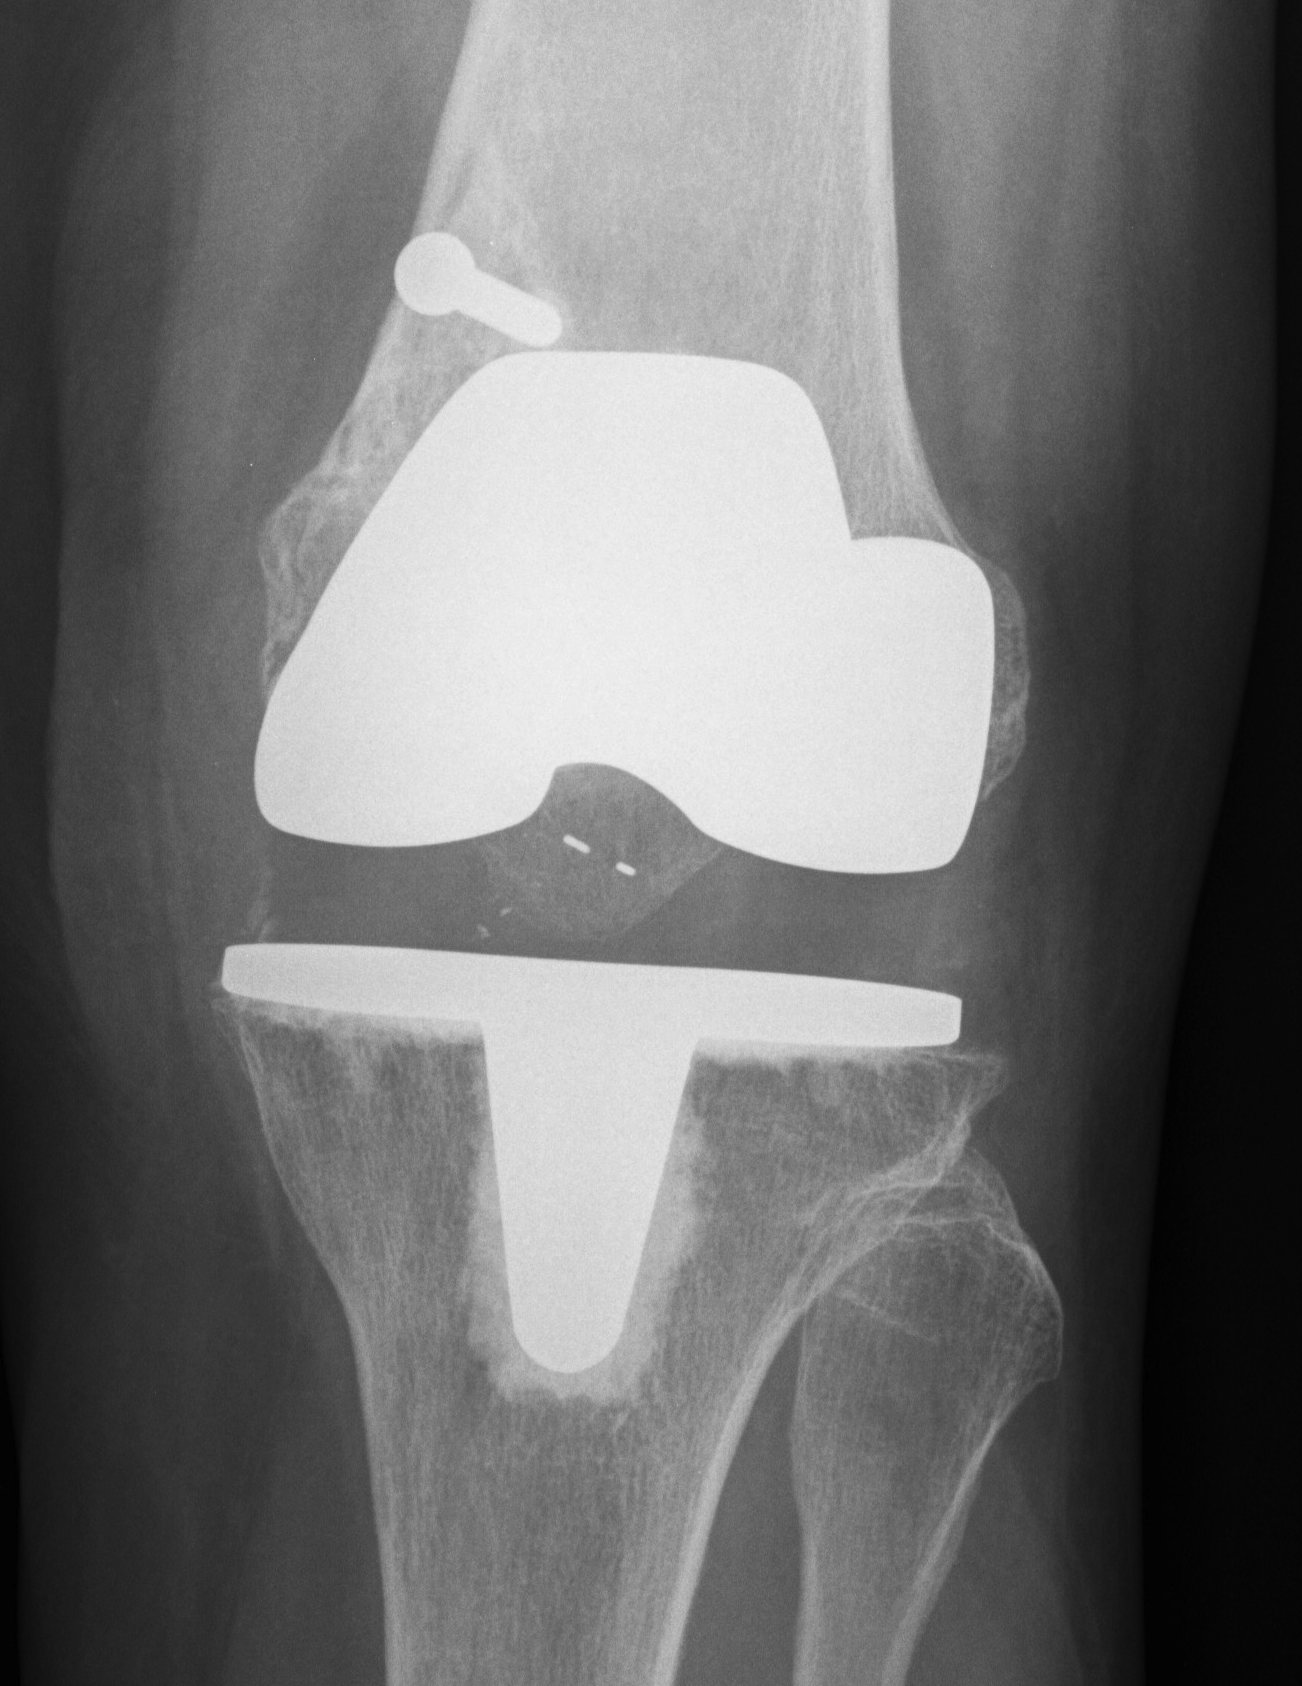

TKR Periprosthetic Fracture Minimall Dislplaced CTTKR Periprosthetic Fracture Locking Plate APTKR Periprosthetic Fracture Locking Plate Lateral

Technique

Minimally invasive technique

- may need unicortical screws distally

Results

Kolb et al J Trauma 2010

- 19 patients treated with LISS plate

- 2 delayed union

- otherwise good union rate with minimal complications and good ROM

Streubel JBJS Br 2010

- compared proximal fractures to distal (beyond the femoral prosthesis)

- showed similar healing rates in each group treated with locking plates